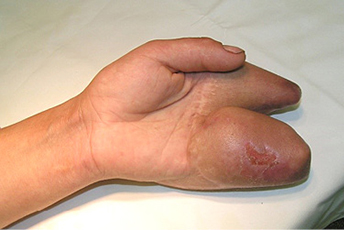

3 pav.

4 pav.

Priekinė ir šoninė kairės plaštakos rentgenograma. Stebimi II ir V pirštų kauliniai defektai per proksimalinį interfalanginį sąnarį (3 ir 4 pav.)